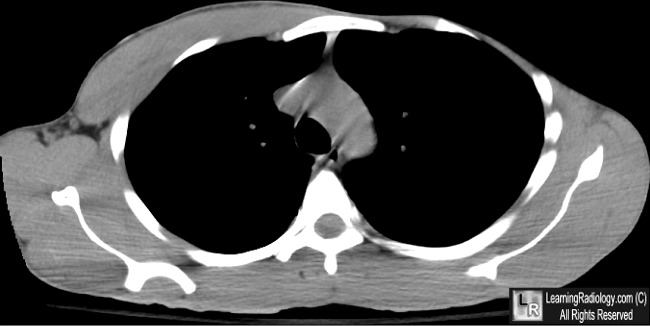

Unilateral Complete Congenital Serratus Anterior Muscle ...

Winged scapula. CASE PRESENTATION A 28-year-old white man was referred to the authors’ outpatient clinic by his primary care Congenital abnormalities of the scapula are not uncom-mon; however, little is known of the embryologic origin of ... Fetch Doc